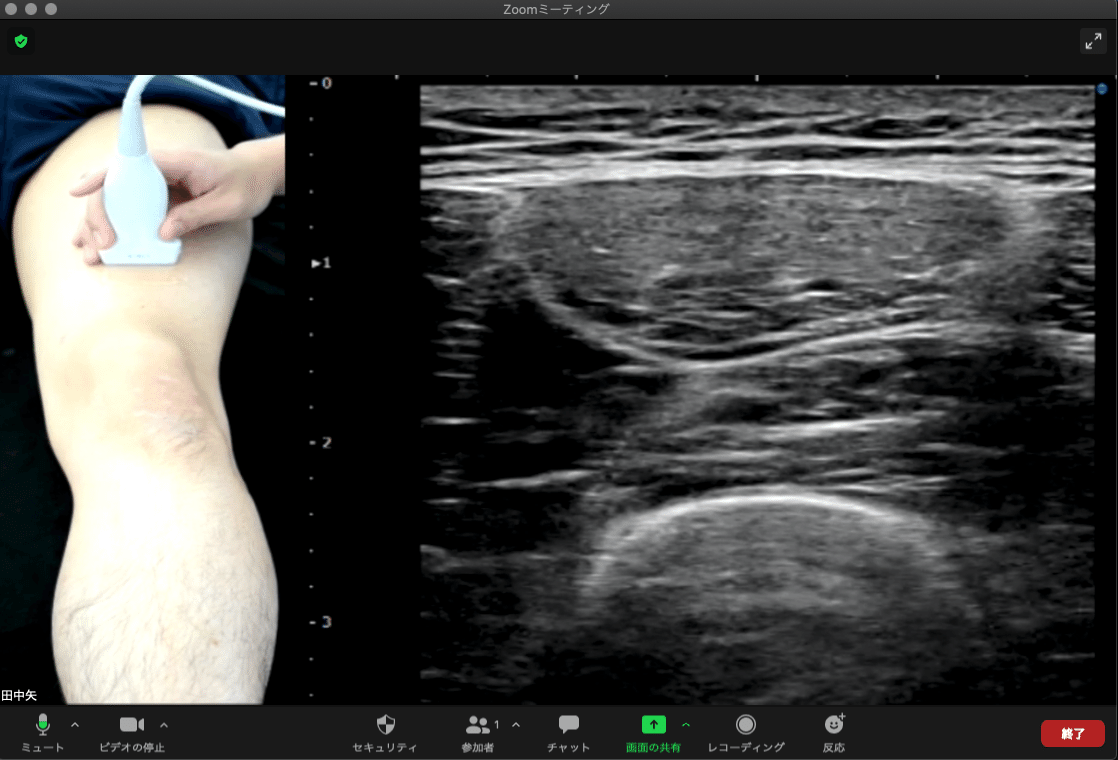

↑この画像はいつも皆さんが使用しているzoomの画面(ビデオ設定の△をクリックした時)です。

現在はビデオ設定が『FaceTime HDカメラ(内臓)』になっているので自分が映っていることが確認できるかと思います。

通常、接続可能なカメラを選択する事ができるかと思います。先ほど『仮想カメラ開始』をクリックしているので『OBS Virtual Camera』が選択できる状態になっています。

もし『OBS Virtual Camera』が表示されなければOBSがインストールされていないかクリックされていないと思われます。

選択すると下図の様に画面が変わります。

この設定を行うことで先ほどまで自分が映っていた画面がOBSの画面に切り替わります。

この設定でわざわざ画面共有を行わずともエコーの画面を共有する事が可能となります。

こんなことが可能になります。

二人で画面を確認しながらエコーの練習ができます。